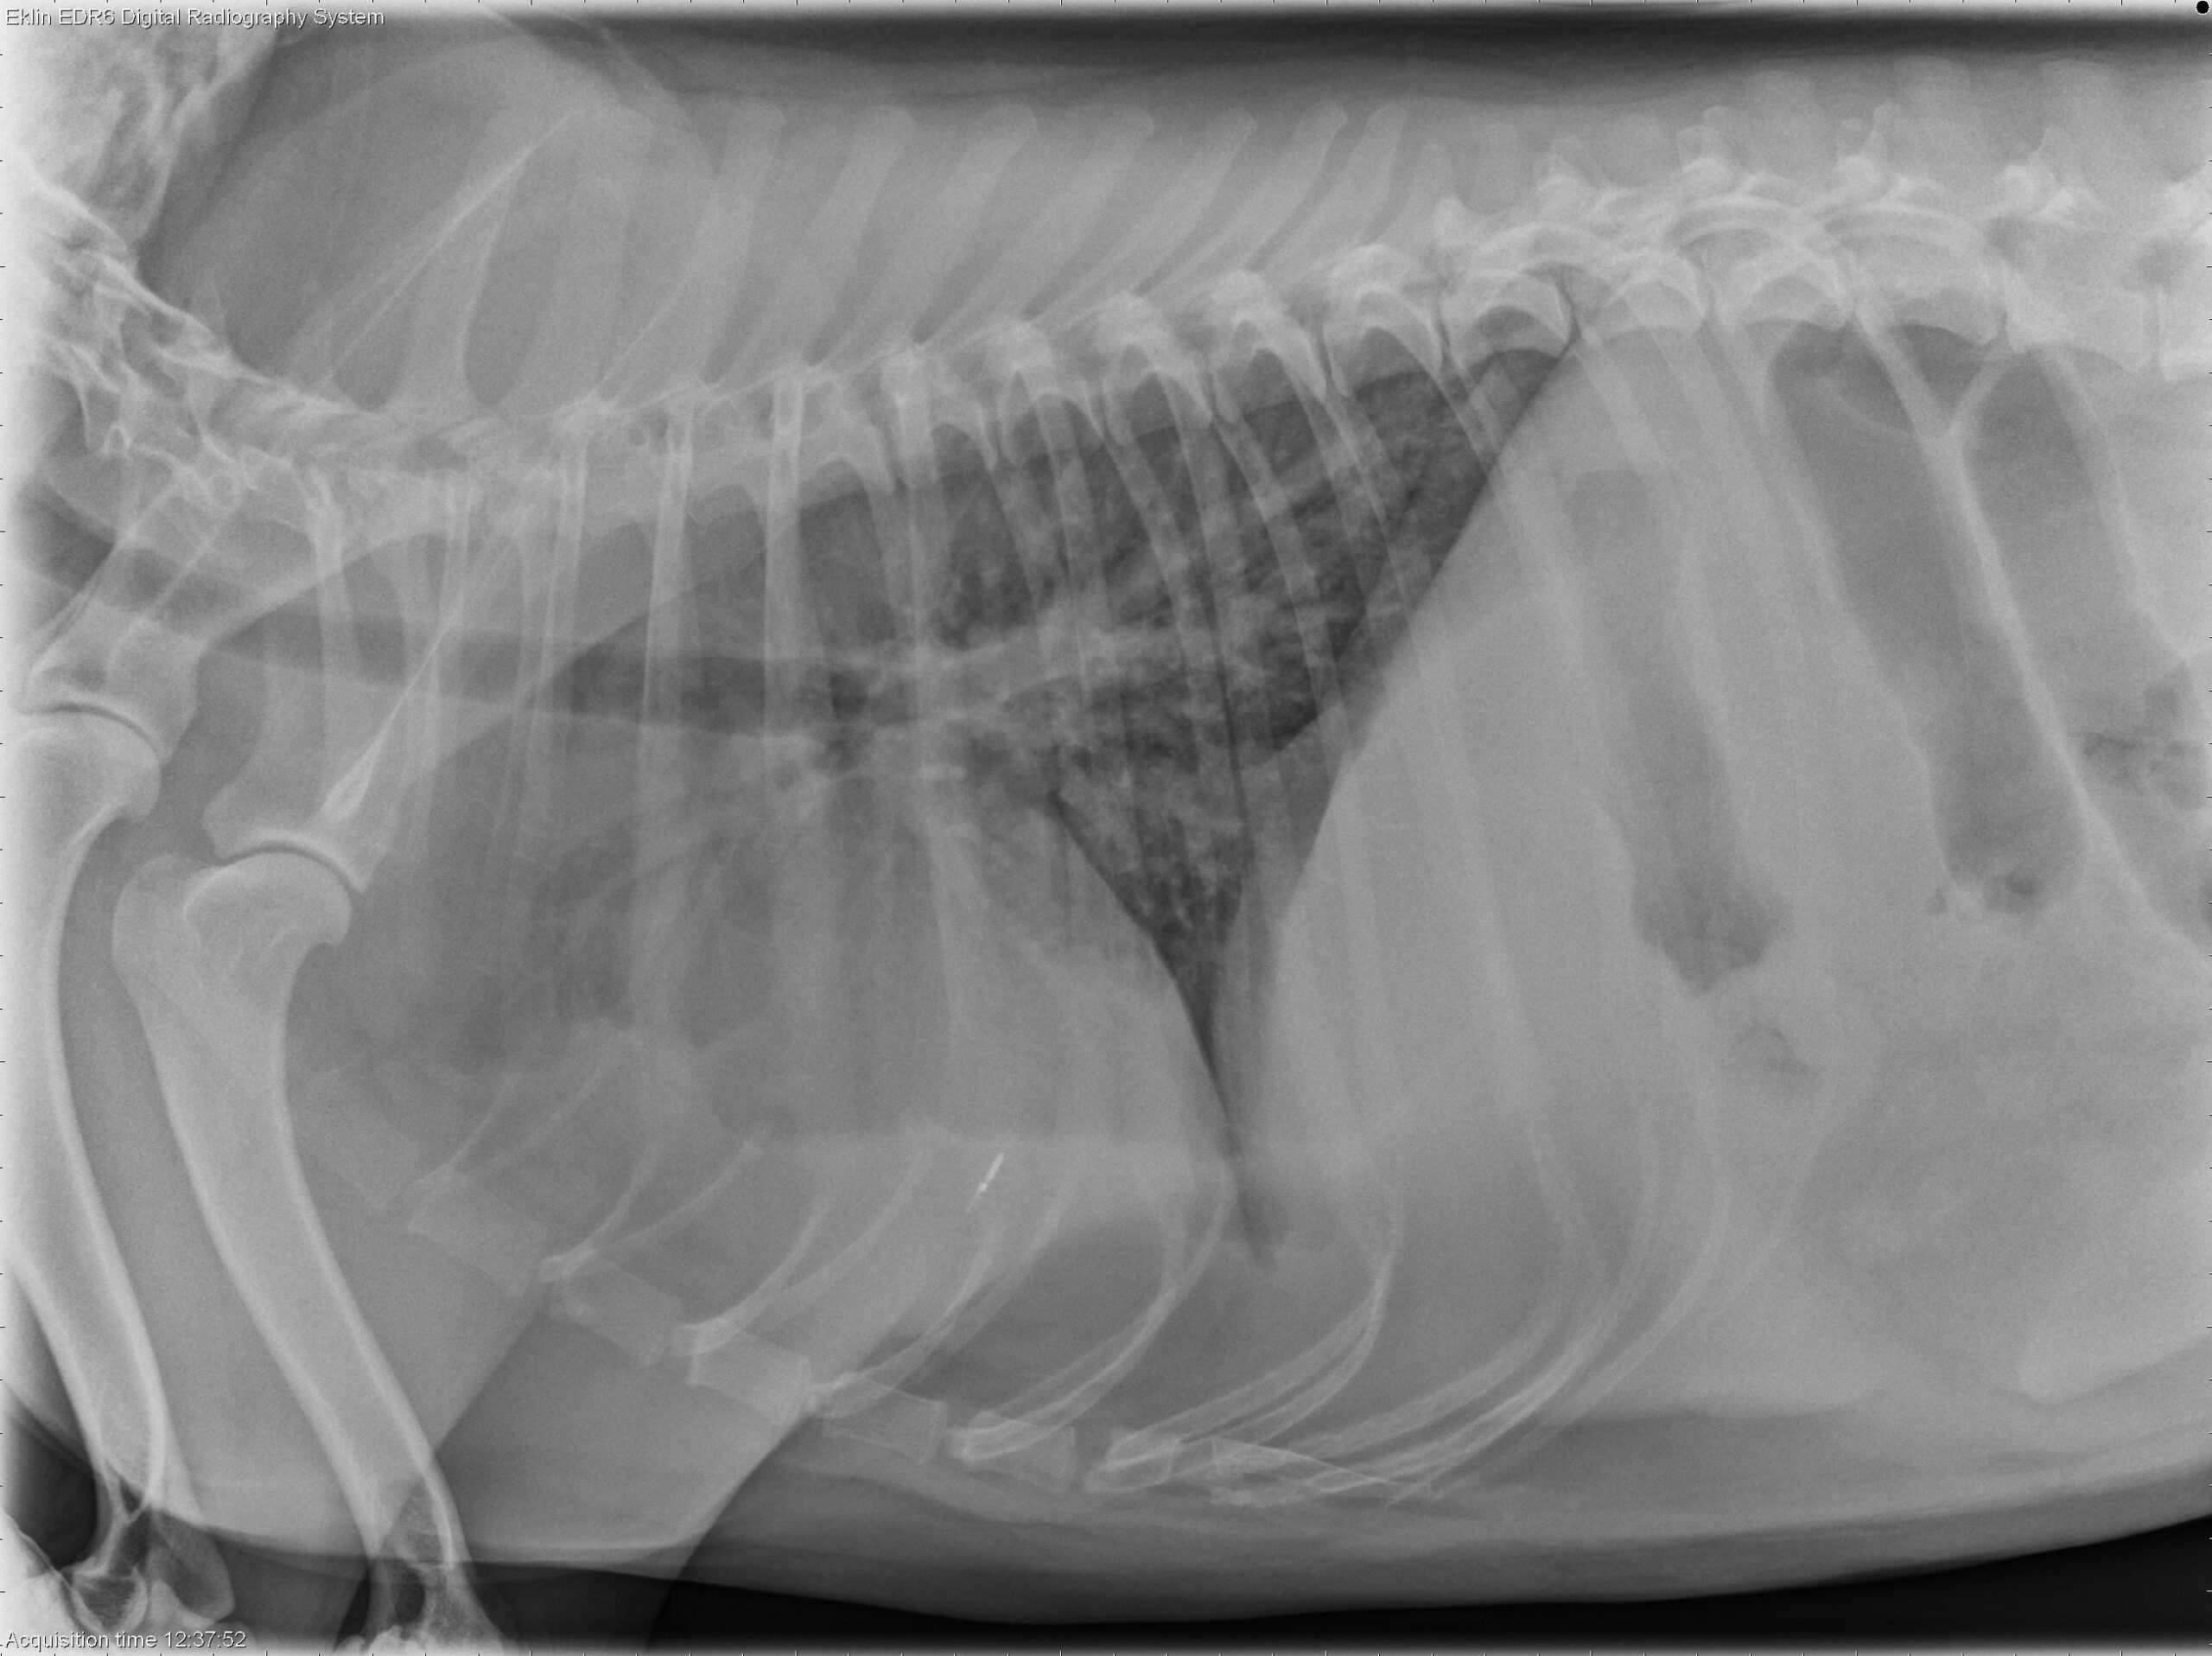

A 4-year-old spayed female Labrador Retriever is presented with fever of unknown origin (FUO).

Thorax: There is increased soft tissue opacity within the pleural space, with retraction of the lung lobes and partial silhouetting with the cardiac silhouette, consistent with pleural effusion. A patchy broncho-interstitial pattern is present in the lungs. The cardiovascular structures appear normal.

Bicavitary effusion may result from round cell neoplasia, metabolic disorders, or inflammatory diseases. The hepatosplenomegaly is most suggestive of lymphoma. Differential diagnoses for the pulmonary pattern include lymphoma and non-cardiogenic pulmonary edema.

Ultrasound-guided fine-needle aspirates of the liver and spleen were obtained. Cytology confirmed hepatosplenic large granular cell lymphoma (NK-cell type). Thoracic POCUS revealed the presence of pleural effusion and B-lines within the lung parenchyma, indicative of pulmonary fluid accumulation. This suggests concurrent involvement of the lungs, most likely due to non-cardiogenic pulmonary edema.